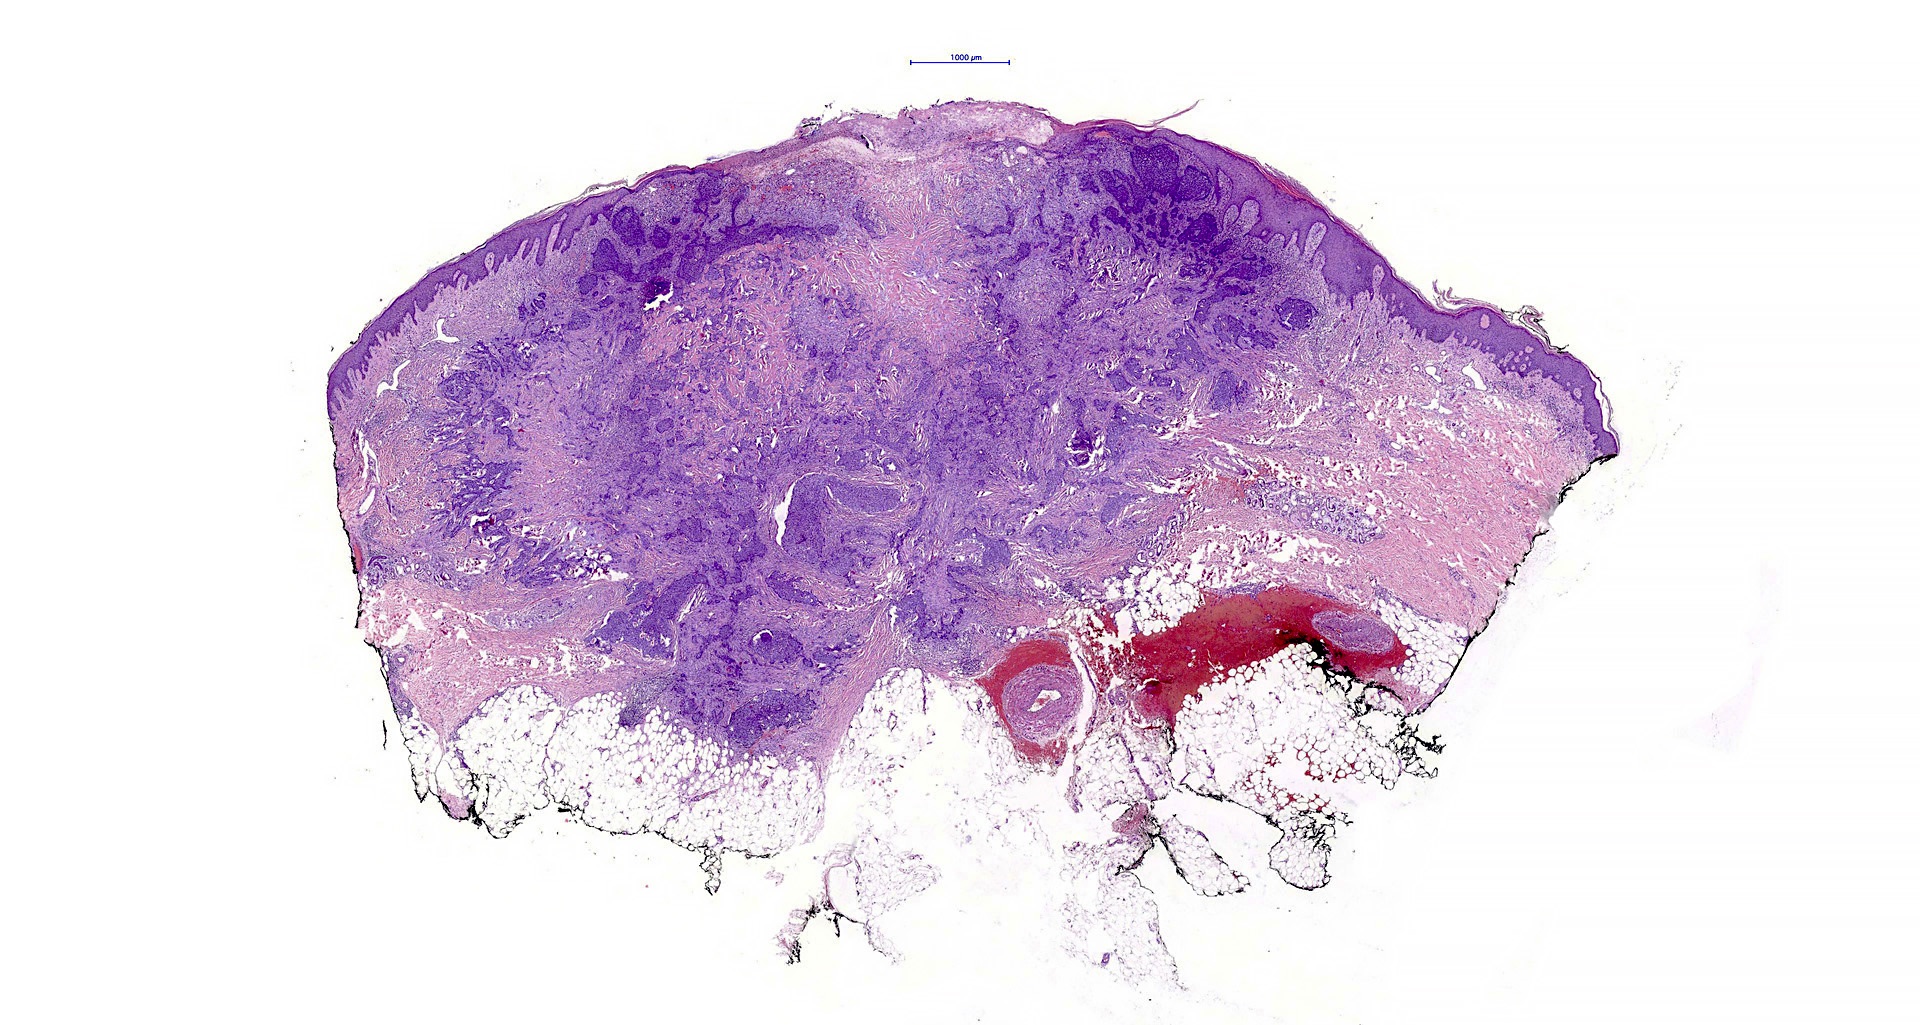

Common variants (Calonje: McKee's Pathology of the Skin, 5th Edition, 2019)

- Nodular and nodulocystic BCC

- Relatively circumscribed mass

- Epidermal or follicular attachment variably present

- Large basaloid lobules with peripheral nuclear palisade

- Lobules may be solid or show central cyst formation due to excessive mucin production

- Fibromyxoid stroma

- Cleft formation between tumor lobules and stroma

- Pleomorphism is generally mild

- Variable mitotic activity and apoptosis

- Sometimes necrosis en masse